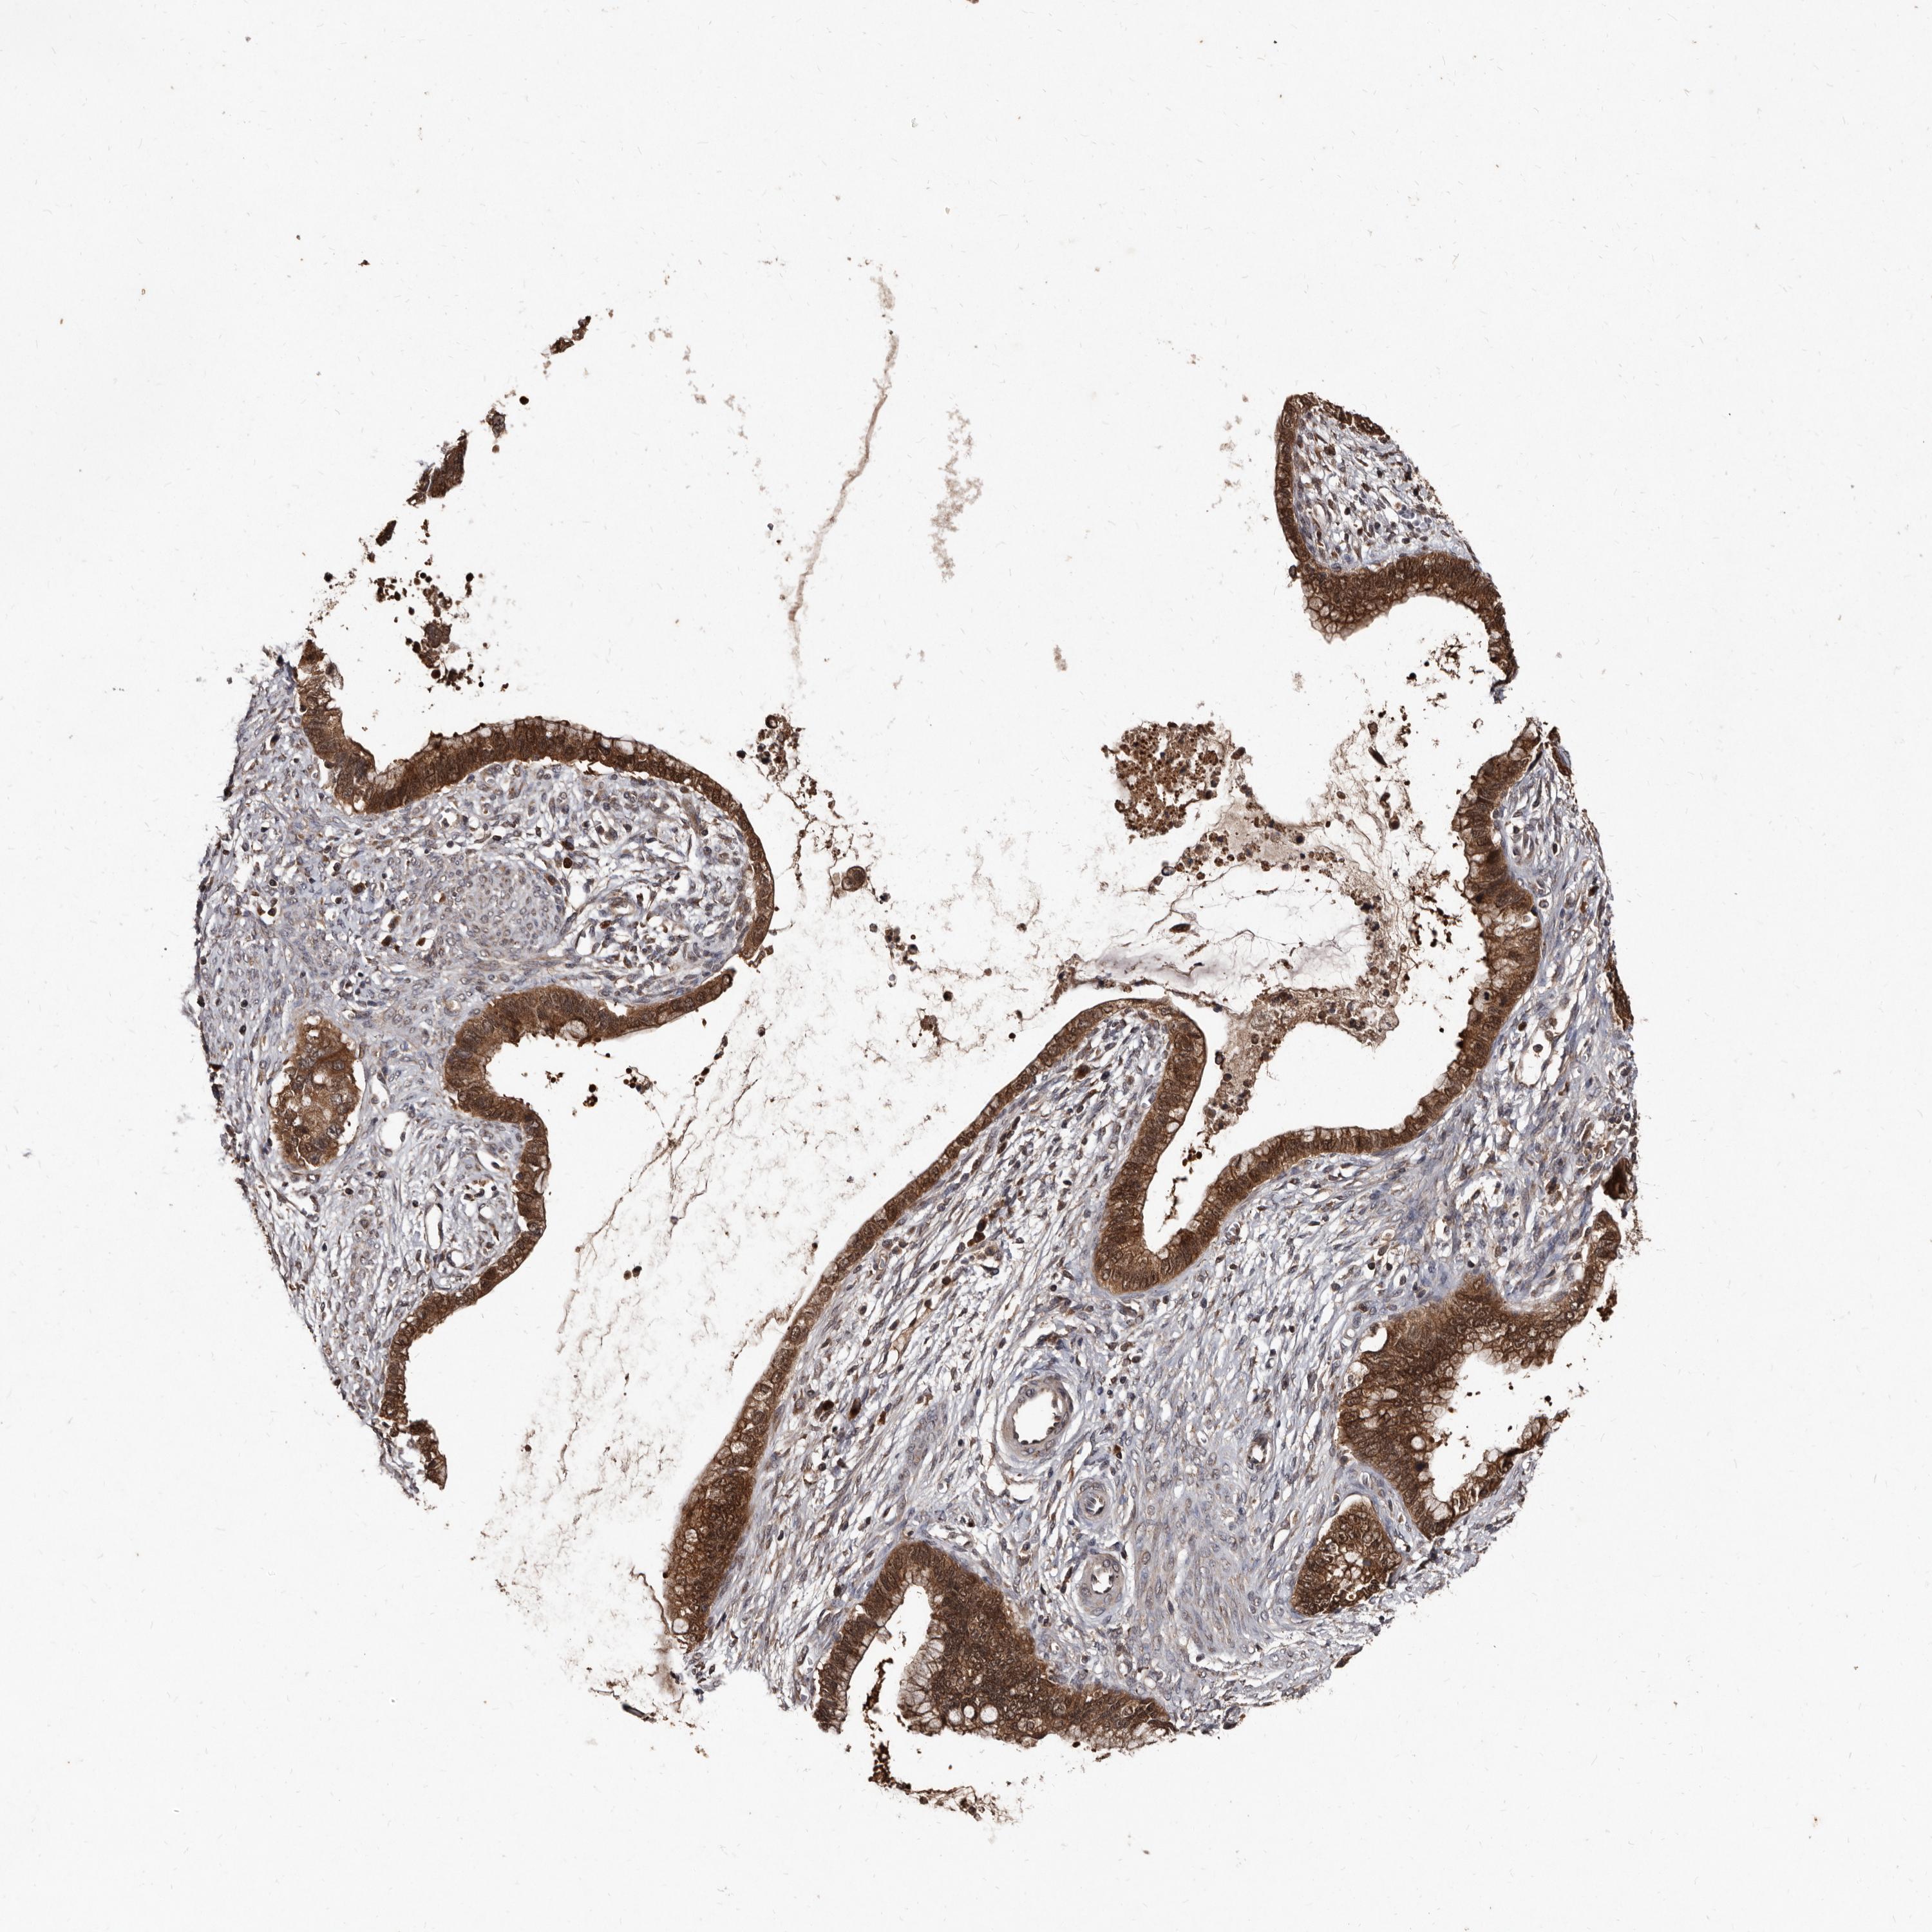

CERVICAL CANCER - Protein expressioni

A mouse-over function shows sample information and annotation data. Click on an image to view it in a full screen mode. Samples can be filtered based on level of antibody staining by selecting one or several of the following categories: high, medium, low and not detected. The assay and annotation is described here.

Note that samples used for immunohistochemistry by the Human Protein Atlas do not correspond to samples in the TCGA dataset.

Antibody stainingi

Antibody staining in the annotated cell types in the current human tissue is reported as not detected, low, medium, or high, based on conventional immunohistochemistry profiling in selected tissues. This score is based on the combination of the staining intensity and fraction of stained cells.

Each image is clickable and will lead to virtual microscopy that enables deeper exploration of all samples and also displays staining intensity scores, fraction scores and subcellular localization as well as patient and tissue information for each sample.

Antibody HPA029900

Staining

High

Medium

Low

Not detected

Intensity

Strong

Moderate

Weak

Negative

Quantity

>75%

75%-25%

<25%

None

Location

Nuclear

Cytoplasmic/membranous

Cytoplasmic/membranous,nuclear

Squamous cell carcinoma, NOS

Adenocarcinoma, NOS